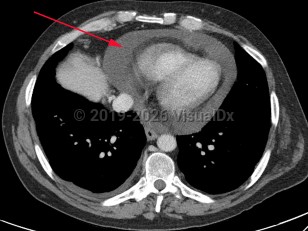

Pericardial effusion

A pericardial effusion (PE) is an accumulation of an abnormal amount of fluid within the pericardial cavity, usually from inflammation. It may be caused by local or systemic disorders or may be idiopathic. It is typically secondary to injury to the pericardium, such as pericarditis. In more than half of cases, PE is associated with a known or suspected underlying process.

A potentially life-threatening complication of pericardial effusion is cardiac tamponade, a condition where there is poor blood circulation and an insufficient amount of oxygen to the body.